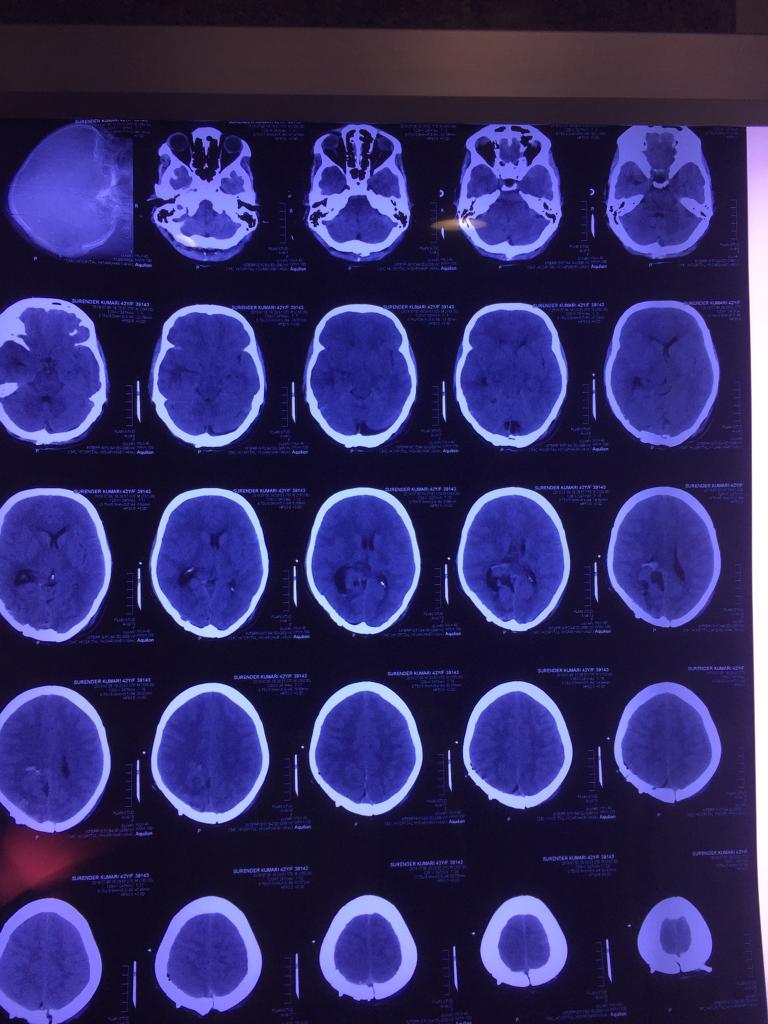

Cases